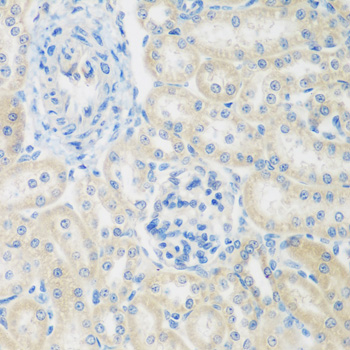

Immunohistochemistry of paraffin-embedded rat kidney using ENPEP antibody.